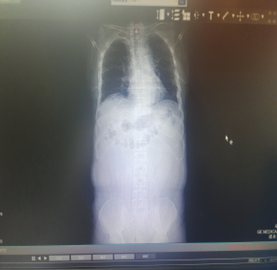

近日,我院胃腸專(zhuān)科接診了一位77歲老年患者,患者半月前確診乙狀結(jié)腸惡性腫瘤并狹窄,近3天突感腹痛腹脹,伴惡心、嘔吐、排便不暢。腹部立位平片及腹部CT示為急性腸梗阻,針對(duì)患者高齡,梗阻癥狀嚴(yán)重等實(shí)際情況,科室副主任醫(yī)師王曉輝建議為患者行“可過(guò)活檢孔道腸道支架置入術(shù)”。經(jīng)過(guò)完善的術(shù)前檢查,在直乙狀結(jié)腸近乎完全梗阻的情況下,手術(shù)團(tuán)隊(duì)在可視化腸道鉗道下成功置入支架,手術(shù)全程30分鐘左右,術(shù)后復(fù)查腹平片確認(rèn)腸道支架位置良好,未見(jiàn)脫落,患者排便順利,效果立竿見(jiàn)影,患者及家屬非常滿(mǎn)意手術(shù)效果。

術(shù)后